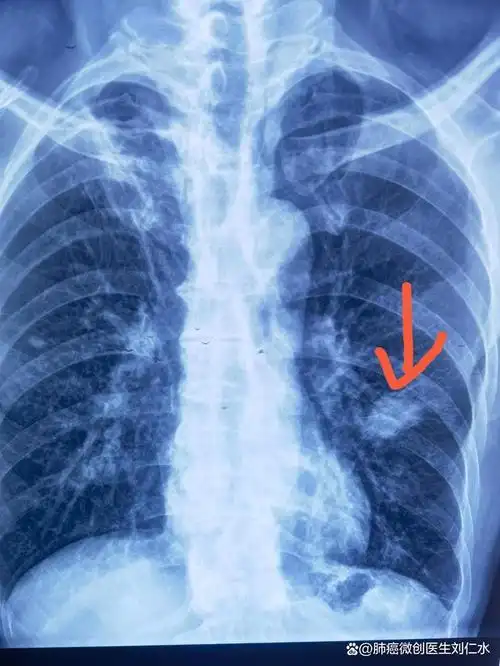

没想到做胸片就发现肺小结节,经过进一步诊断,考虑是肺癌,今天微创